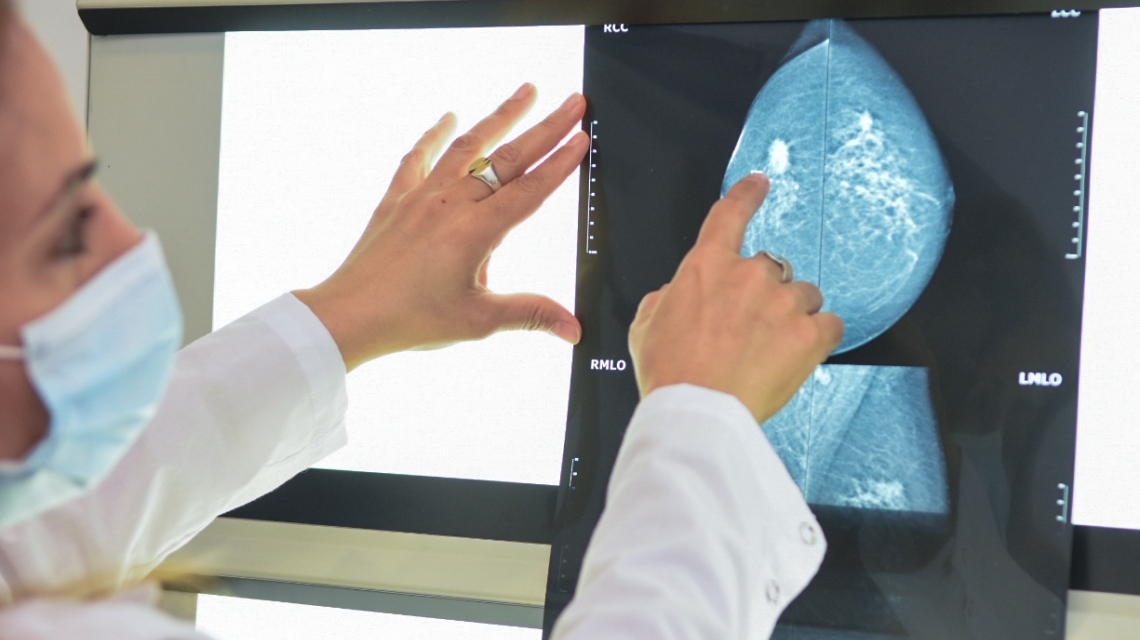

El «Taller de Tumores Hereditarios» dictado por el programa de Cáncer Heredo-Familiar de la Agencia de Control del Cáncer, está destinado a médicos de diferentes especialidades (generalistas, pediatras, ginecólogos, mastólogos, cirujanos, gastroenterólogos, y otros), que estén interesados en formarse sobre epidemiología, diagnóstico, tratamiento y seguimiento de tumores hereditarios más frecuentes en la práctica clínica diaria.

>> 9.10 horas: Generalidades en cáncer hereditario / Cáncer hereditario de mama y ovario. Dr. Gonzalo Tabares.